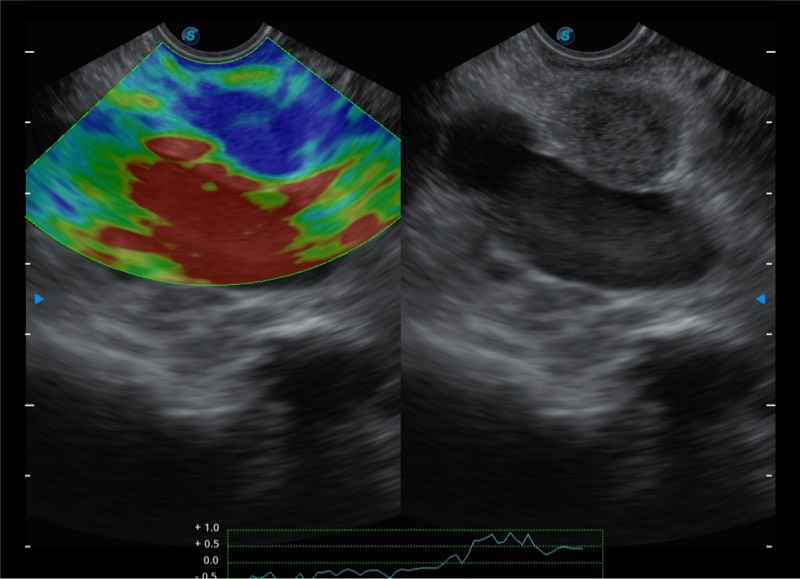

高端超声影像平台

基于二十年的超声技术积累,新葡的京集团8814检测站提供了最新一代的独立超声主机,在提供高质量图像的同时满足多学科使用。具备常见多普勒技术并提供弹性成像、声学造影等高端影像技术。新一代传感器具有更强的抗干扰能力并减少图像伪影。